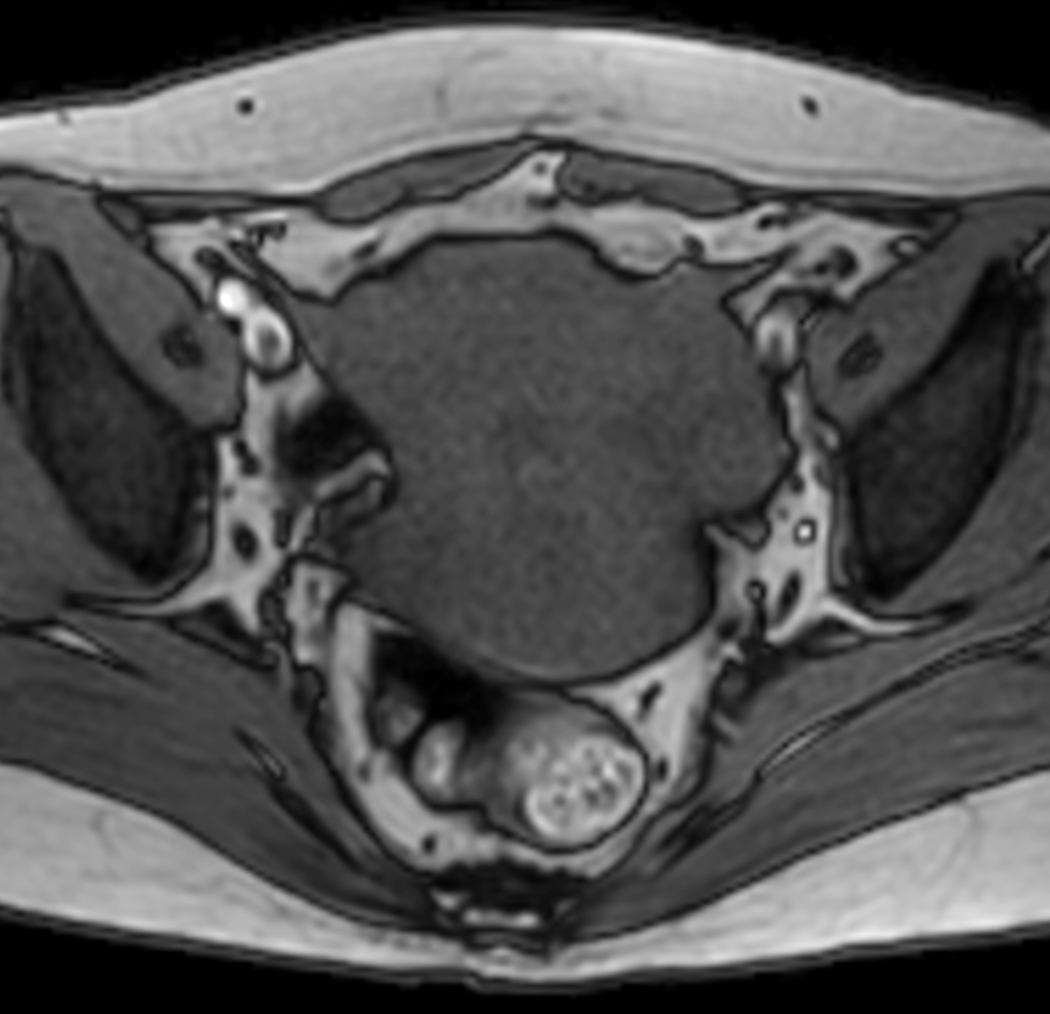

Axial MultiVane XD - T2w TSE

Axial MultiVane XD - T1w TSE